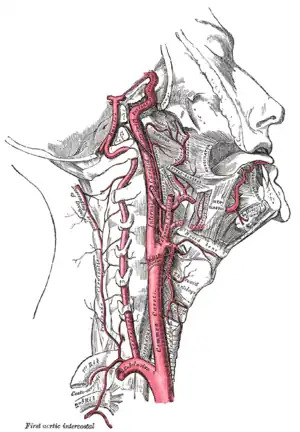

L'artère carotide interne (aussi appelée carotide interne droite ou CID) est une artère issue de l'artère carotide commune, de la branche externe plus précisément, et vascularisant la plus grande partie du cerveau, l'oreille interne et l'œil.

Dans le cou, elle est située dans la gaine carotidienne, à proximité de la veine jugulaire interne.

Elle pénètre dans la boîte crânienne par le canal carotidien situé dans le rocher (base du crâne) de l'os temporal selon un trajet vertical rétro styloïdien. Puis, dans son trajet pétreux, au niveau du foramen déchiré, elle donne dans le crâne une première branche collatérale qui est l'artère carotico-tympanique. En suivant, elle va transpercer le sinus caverneux, sortir par son toit et donner les dernières branches collatérales qui naissent près de la terminaison ; nous retrouvons l'artère cérébrale antérieure qui donnera l'artère hypophysaire supérieure ainsi que l'artère ophtalmique. De plus, dans cette région cérébrale, l'artère carotide interne va s'anastomoser avec l'artère cérébrale postérieure (dérivant de l'artère vertébrale) pour donner l'artère cérébrale moyenne du polygone de Willis.